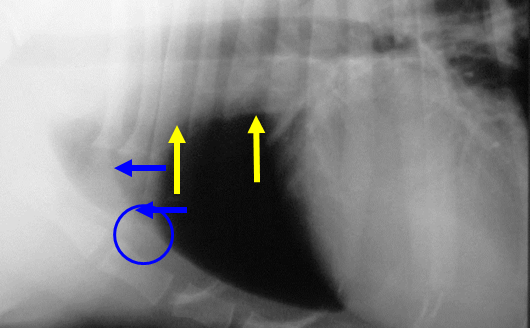

What is labelled here?

Yellow arrows: cranial mediastinum

Blue arrows – can see margins between 2 lung lobes as there is a fold of mediastinum going in between the 2 lung lobes and if this margin is transverse whilst doing a lateral view, will see it